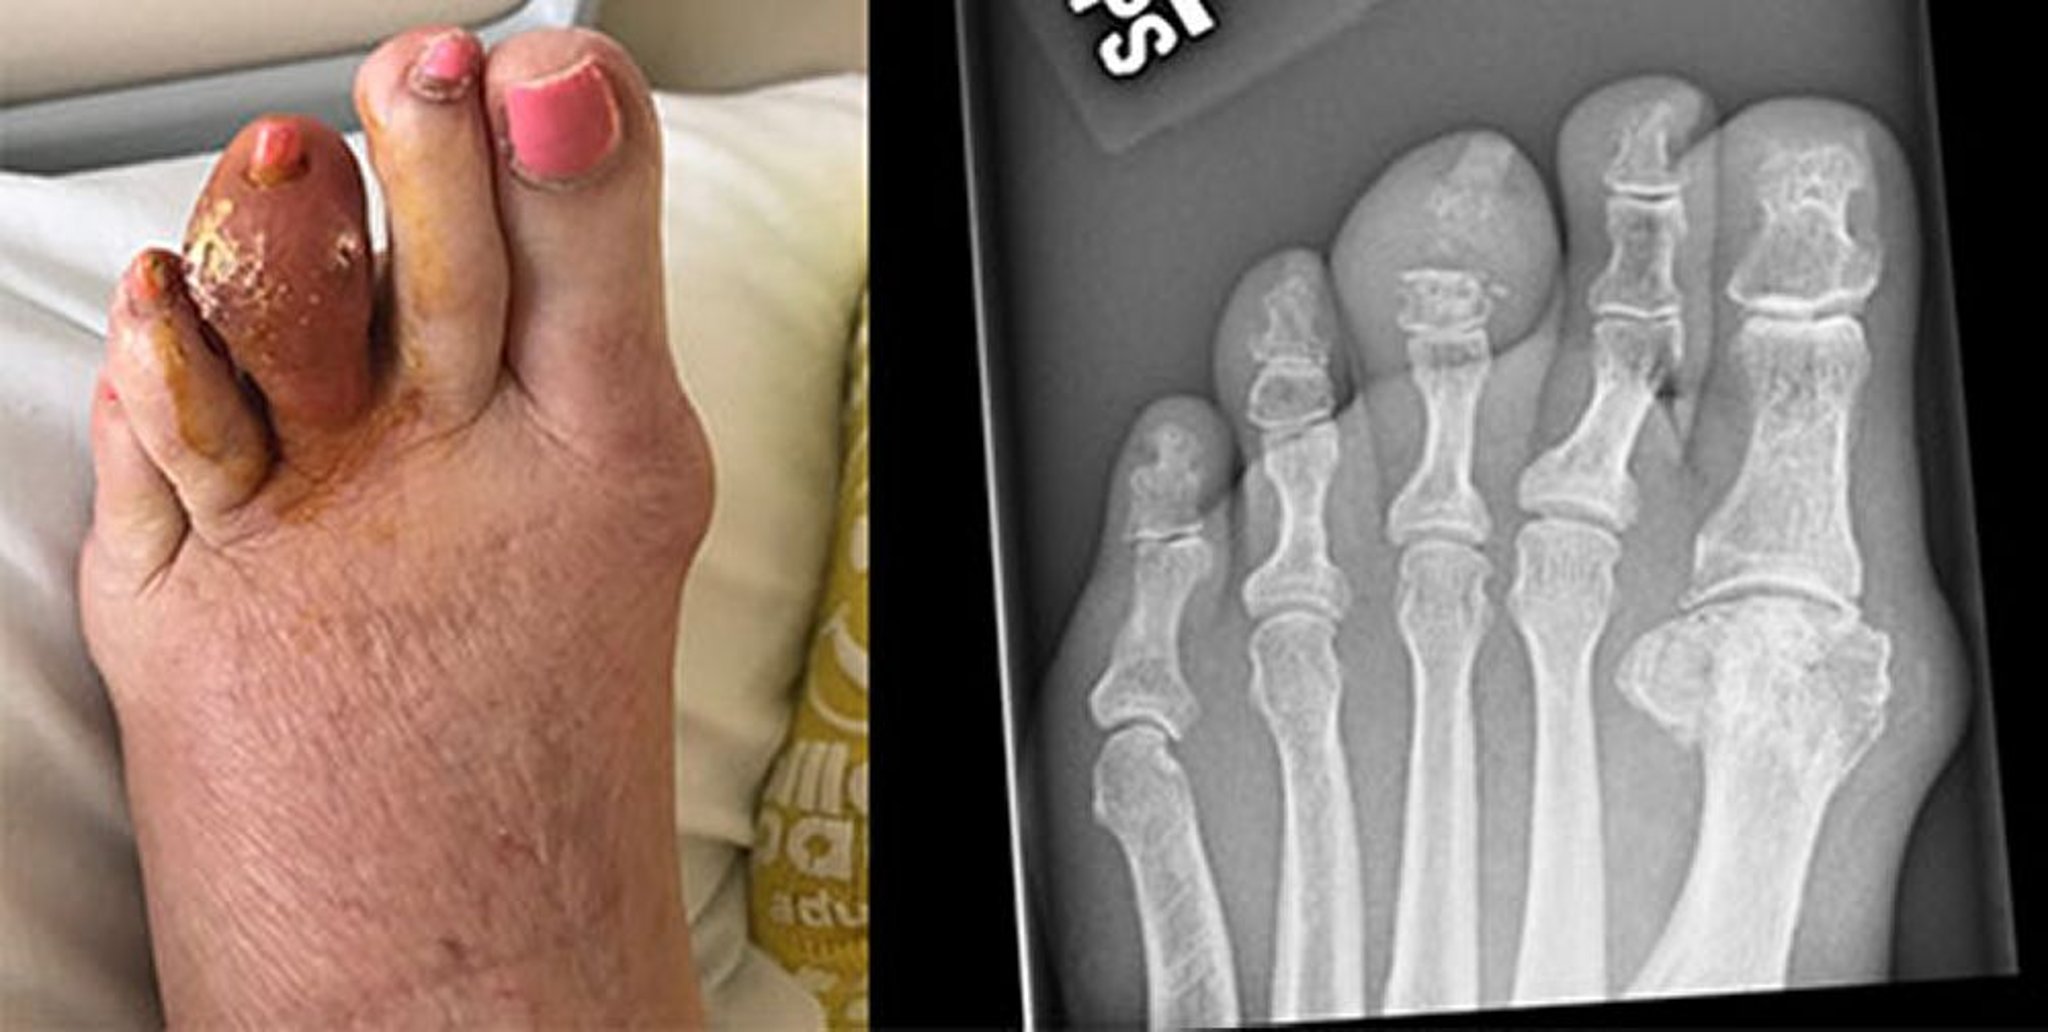

L'artrite gottosa acuta generalmente esordisce con un improvviso dolore (spesso notturno). Il più delle volte viene coinvolta l'articolazione metatarsofalangea dell'alluce (la cosiddetta podagra), ma anche il collo del piede, la caviglia, il ginocchio, il polso e il gomito sono sedi frequenti. Raramente sono coinvolte le articolazioni coxo-femorale, della spalla, sacroiliaca, sternoclavicolare o della colonna cervicale. Il dolore diviene progressivamente più intenso, in genere nel giro di alcune ore, e spesso è intollerabile. La tumefazione, il calore, l'arrossamento e la dolorabilità selettiva possono suggerire un'infezione. La cute sovrastante può divenire tesa, calda, lucida e di colore rosso o violaceo. Talvolta compaiono febbre, tachicardia, brividi e malessere.

Tofi

I tofi palpabili si sviluppano in pazienti con gotta e possono raramente presentarsi in pazienti che non hanno mai avuto un'artrite gottosa acuta. Sono in genere papule o noduli solidi gialli o bianchi, singoli o multipli. Si possono sviluppare in diverse sedi, normalmente dita, mani, piedi e attorno all'olecrano o al tendine di Achille. I tofi possono svilupparsi nei reni, in altri organi e nel sottocute delle orecchie. I pazienti con noduli artrosici di Heberden possono formare tofi all'interno dei noduli stessi. Questo sviluppo si verifica il più delle volte nelle donne anziane che assumono diuretici, ed essi possono diventare notevolmente infiammati e mal diagnosticati come artrosi infiammatoria. Normalmente indolori, i tofi, specie nelle borse olecraniche, possono andare incontro a infiammazione acuta e divenire dolenti, spesso dopo un danno non evidente o lieve. Possono ulcerare la cute, determinando la secrezione di masse gessose di cristalli di urato. Queste fistole possono diventare infette. I tofi intra- e periarticolari possono successivamente causare deformità e artrosi secondaria.

L'artrite gottosa cronica deve essere presa in considerazione nei pazienti con persistente malattia articolare inspiegabile o con tofi sottocutanei o ossei. Possono risultare utili RX della 1a articolazione metatarsofalangea o delle altre articolazioni colpite. Queste RX possono mostrare lesioni a stampo nell'osso subcondrale con margini ossei debordanti, soprattutto a livello della prima articolazione metatarsofalangea; le lesioni devono avere un diametro 5 mm per essere visibili alla RX. Lo spazio articolare è tipicamente conservato fino agli stadi tardivi della malattia.